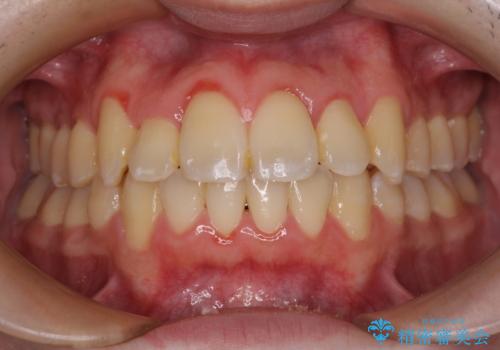

- 上下のデコボコを改善したいとのことで来院された患者様です。

近々妊娠する予定であり、極力短期間で治療したいとのことで、ワイヤー装置による非抜歯矯正治療を行うこととしました。

治療開始後すぐに妊娠され、つわりと闘いながらの矯正治療となりました。

上下顎でゴムかけを行ったのですが、早く終わらすためにしっかりと装着していただき、無事出産前に装置を外すことができました。